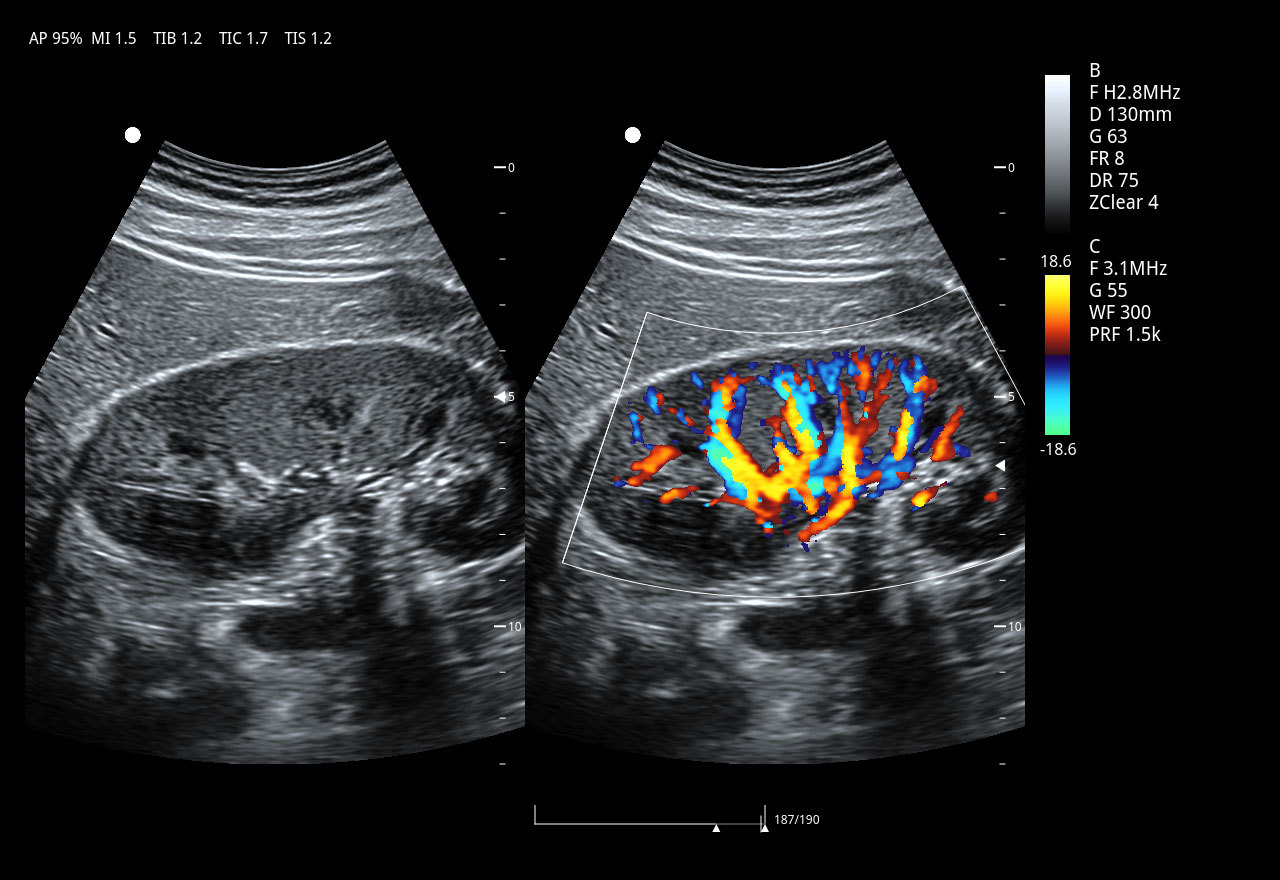

Imágenes clínicas extraordinarias